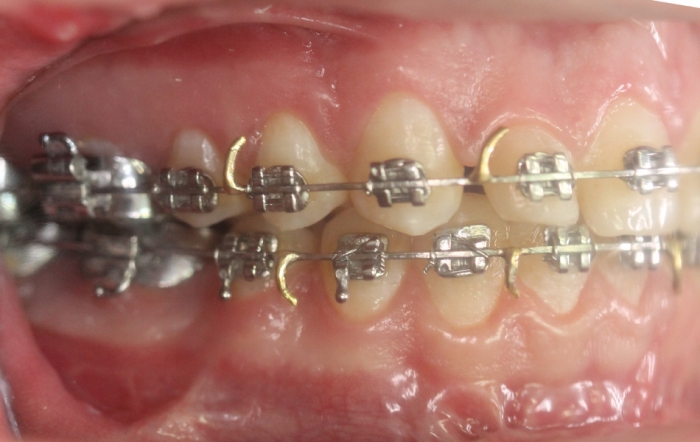

Mordida inicial